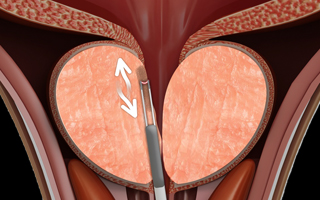

03

3단계

플라즈마 장비를 회전시키며 치료부위를 넓혀줍니다.